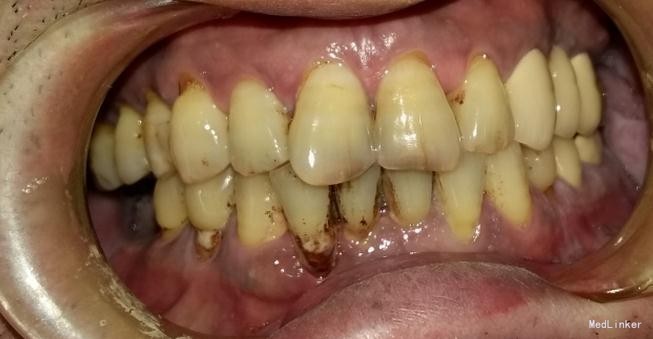

患者,男,45岁,右侧下颌侧切牙严重龋坏,拔除后要求种植修复,平素体质一般,无药物、食物过敏史,无高血压、心脏病等系统病史

牙科CT检查骨量适中,适合种植

种植修复